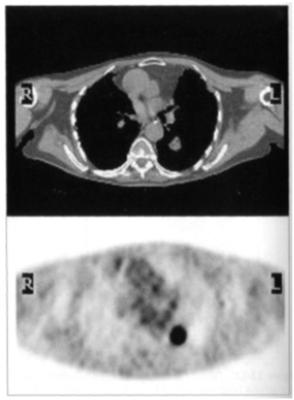

Рис. 9. Компьютерная томограмма (вверху) и ПЭТ– скан (внизу).

У пациента с раком пищевода и мочевого пузыря на ФДГ ПЭТ/КТ сканах в настоящее время представлена